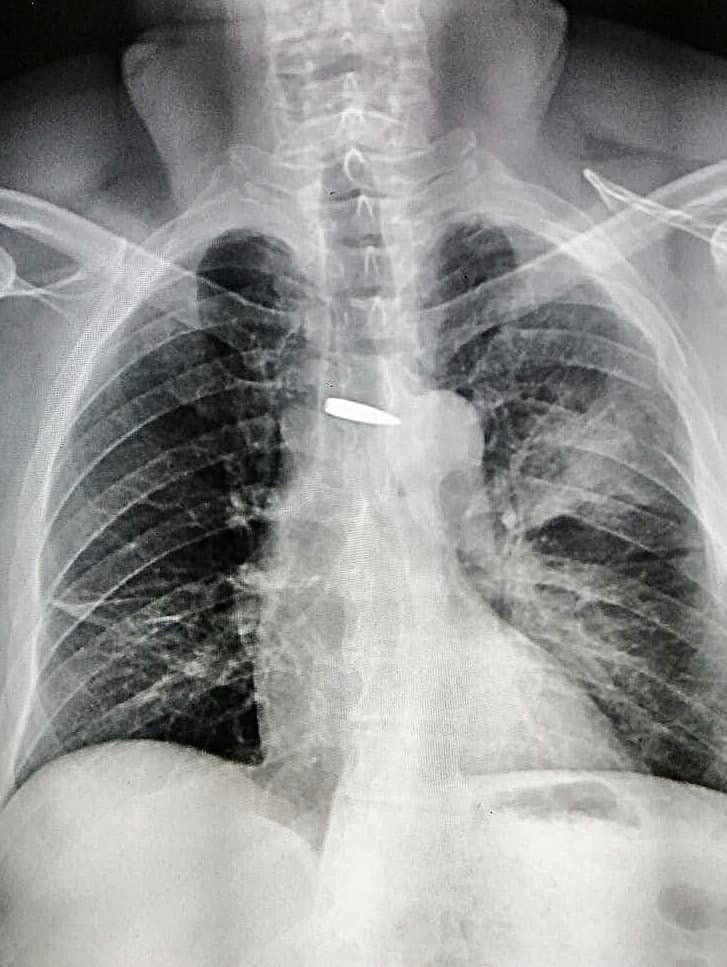

Куля пройшла в міліметрах від серця: хмельницькі медики врятували життя військовому (ФОТО)

Снаряд пройшов крізь ліве плече, ліву легеню та зупинився в міліметрах від серця.

Ворожий снаряд пройшов крізь ліве плече та ліву легеню в міліметрах від серця, роздробив поперечний відросток грудного хребця.

Медики встановили де знаходиться куля до міліметра завдяки новітньому обладнанню, кажуть в міській лікарні. Завдяки цьому, операція пройшла швидко та малотравматично.

Лікарі стабілізували стан пацієнта та поставили дренажну систему в ліву плевральну порожнину. А після цього витягнули снаряд.

— З операційної пацієнт вийшов власними ногами. Куля, яка могла забрати життя військового, була оперативно вилучена та подарована в день народження пацієнту! — додають медики.